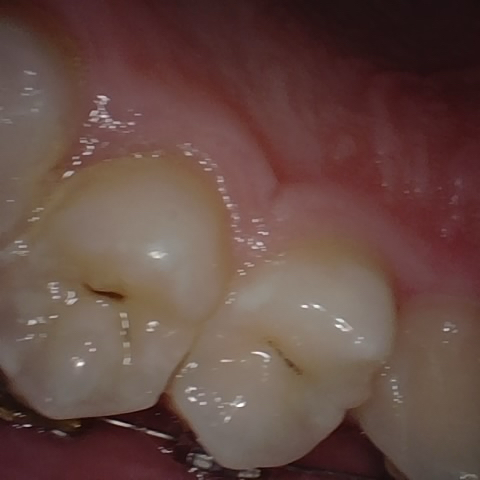

Annotated as "Good"